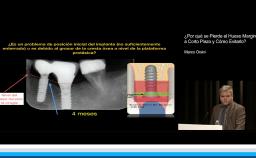

Esta presentación pretende explicar, a través de datos de la literatura, como obtener resultados estéticos con cirugía sin colgajo (flapless). Describe las ventajas del abordaje sin elevación de colgajo en sitios con mucosa ceratinizada y suficiente volumen óseo, así como las limitaciones de la técnica.

Se discuten aspectos fundamentales de los tejidos duros y blandos para obtener resultados predecibles en los casos de instalación inmediata de implantes en alvéolos post extracción (Tipo 1), centrándose en los riesgos y la necesidad de cuidadoso diagnóstico y plan de tratamiento.